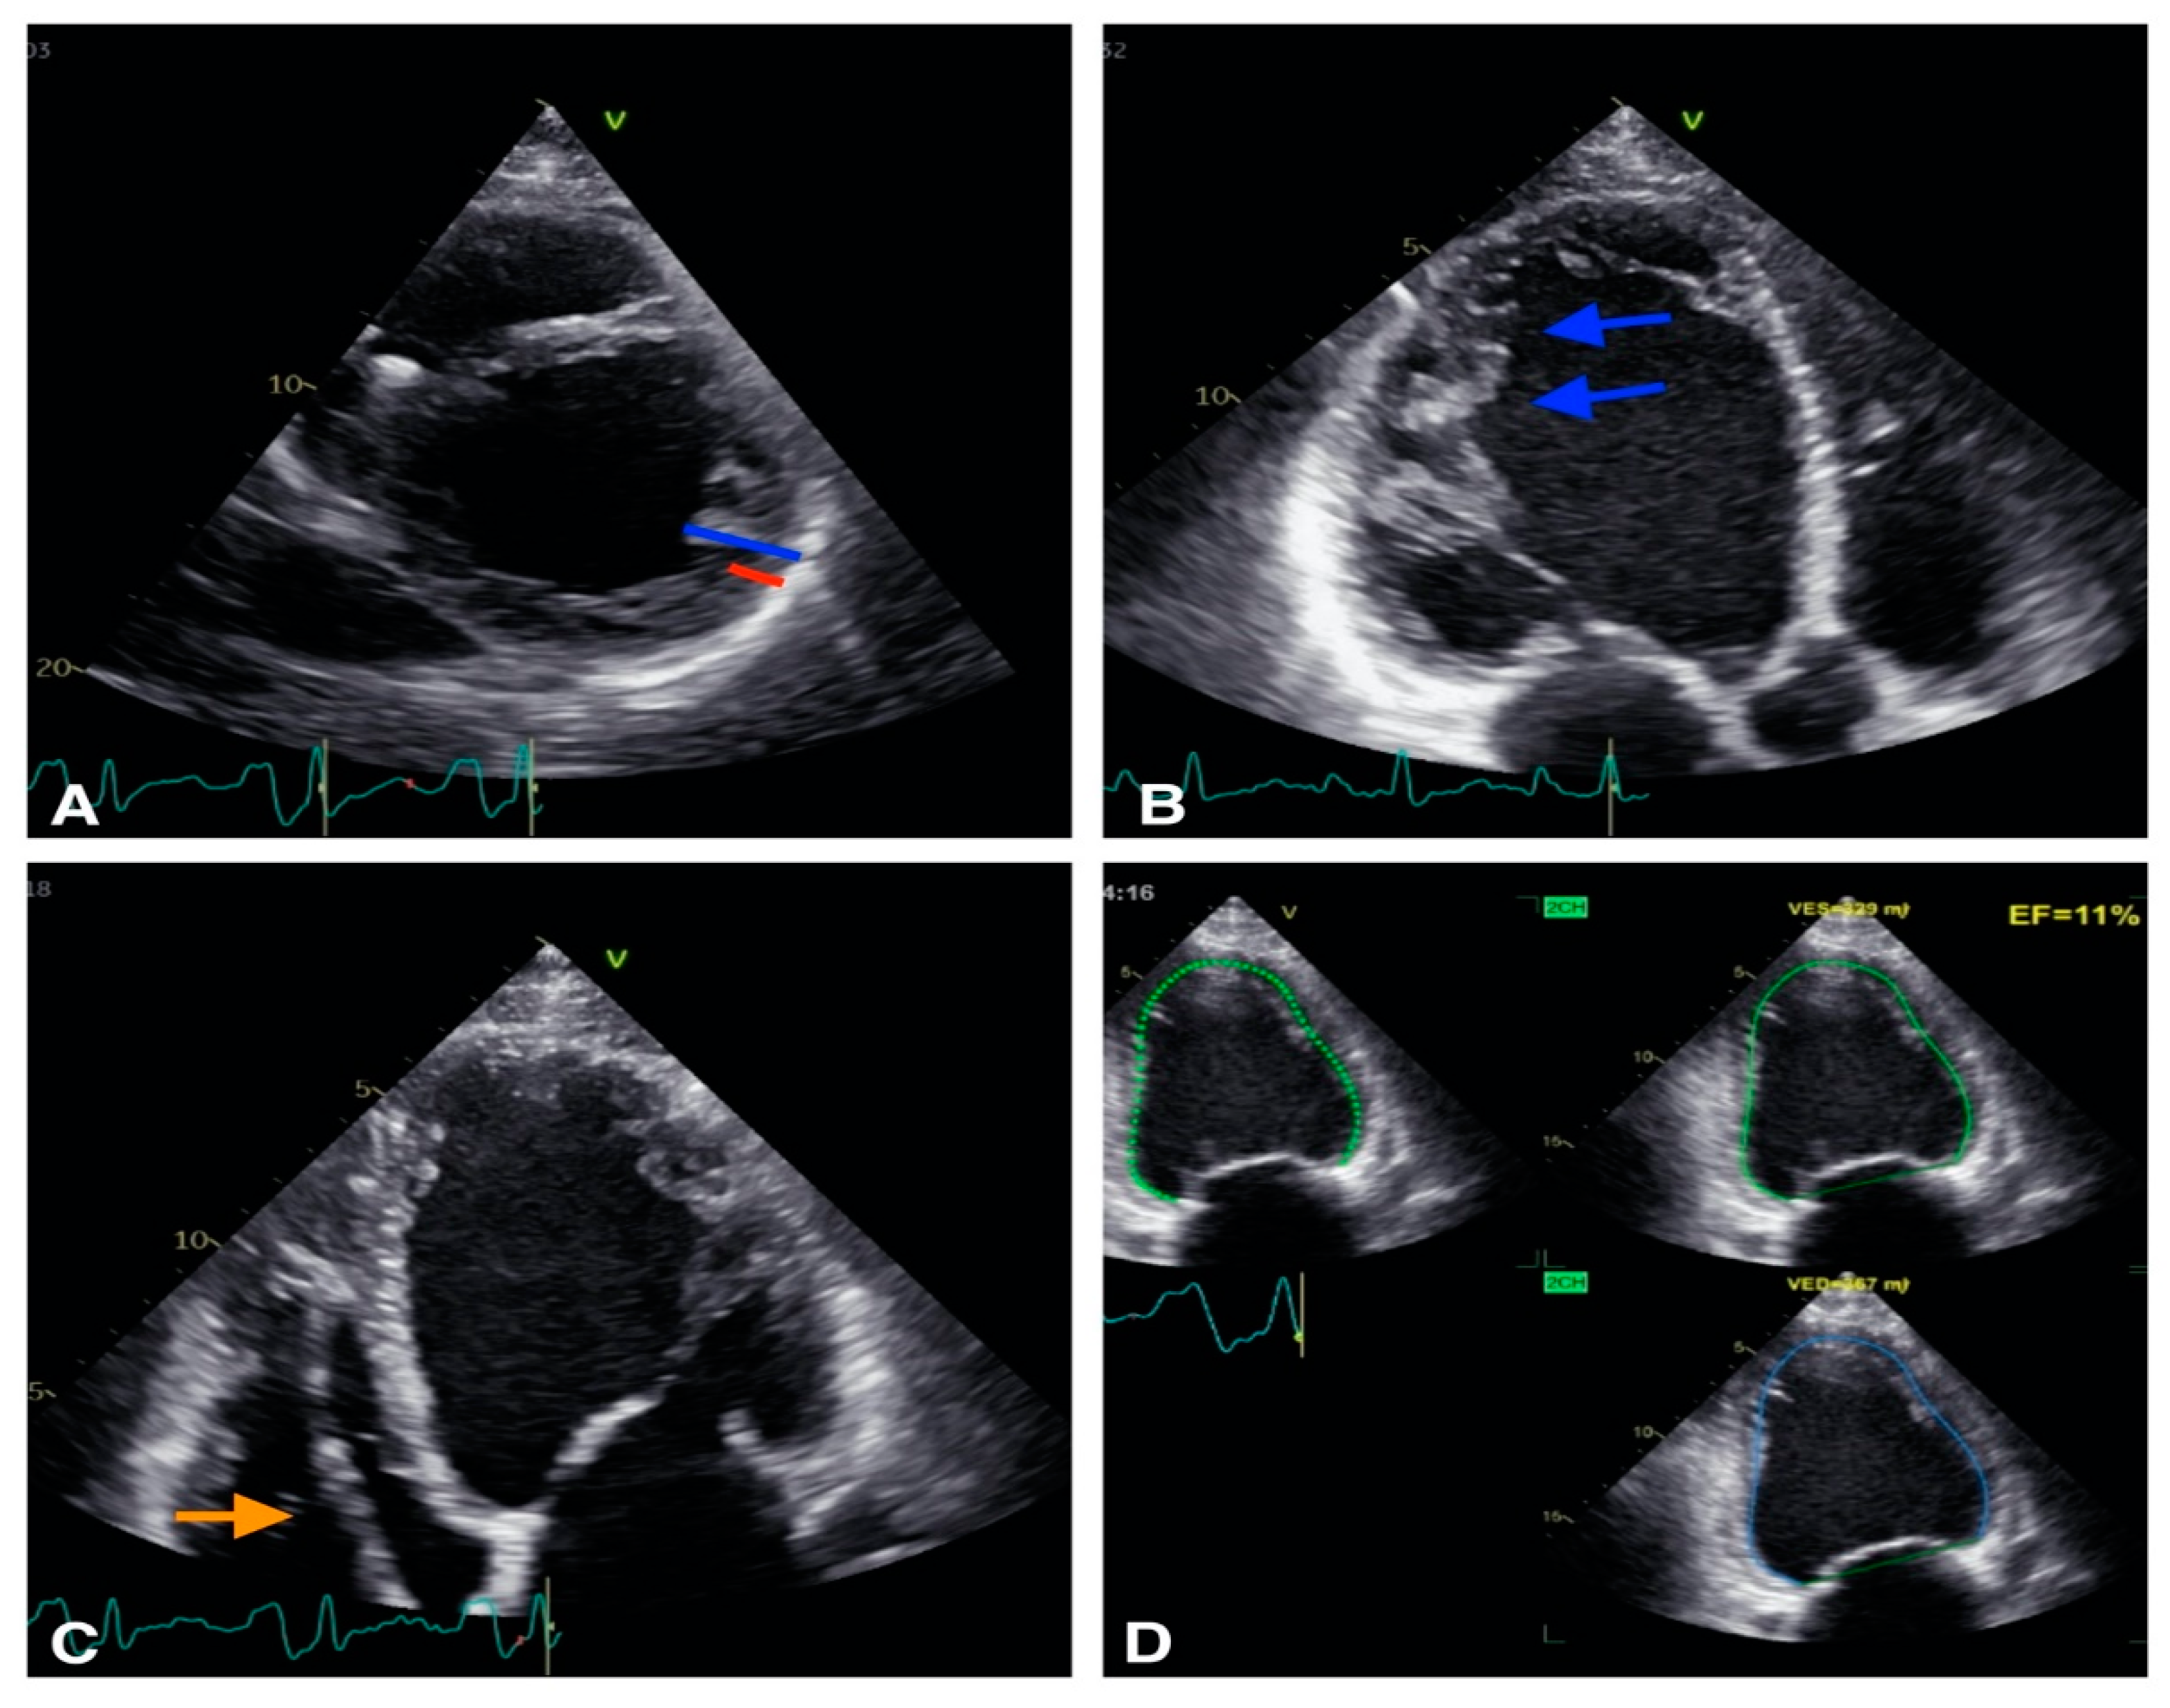

2. Role of Echocardiography in Identification of VA Substrate

2.1. VA in Structural Heart Disease